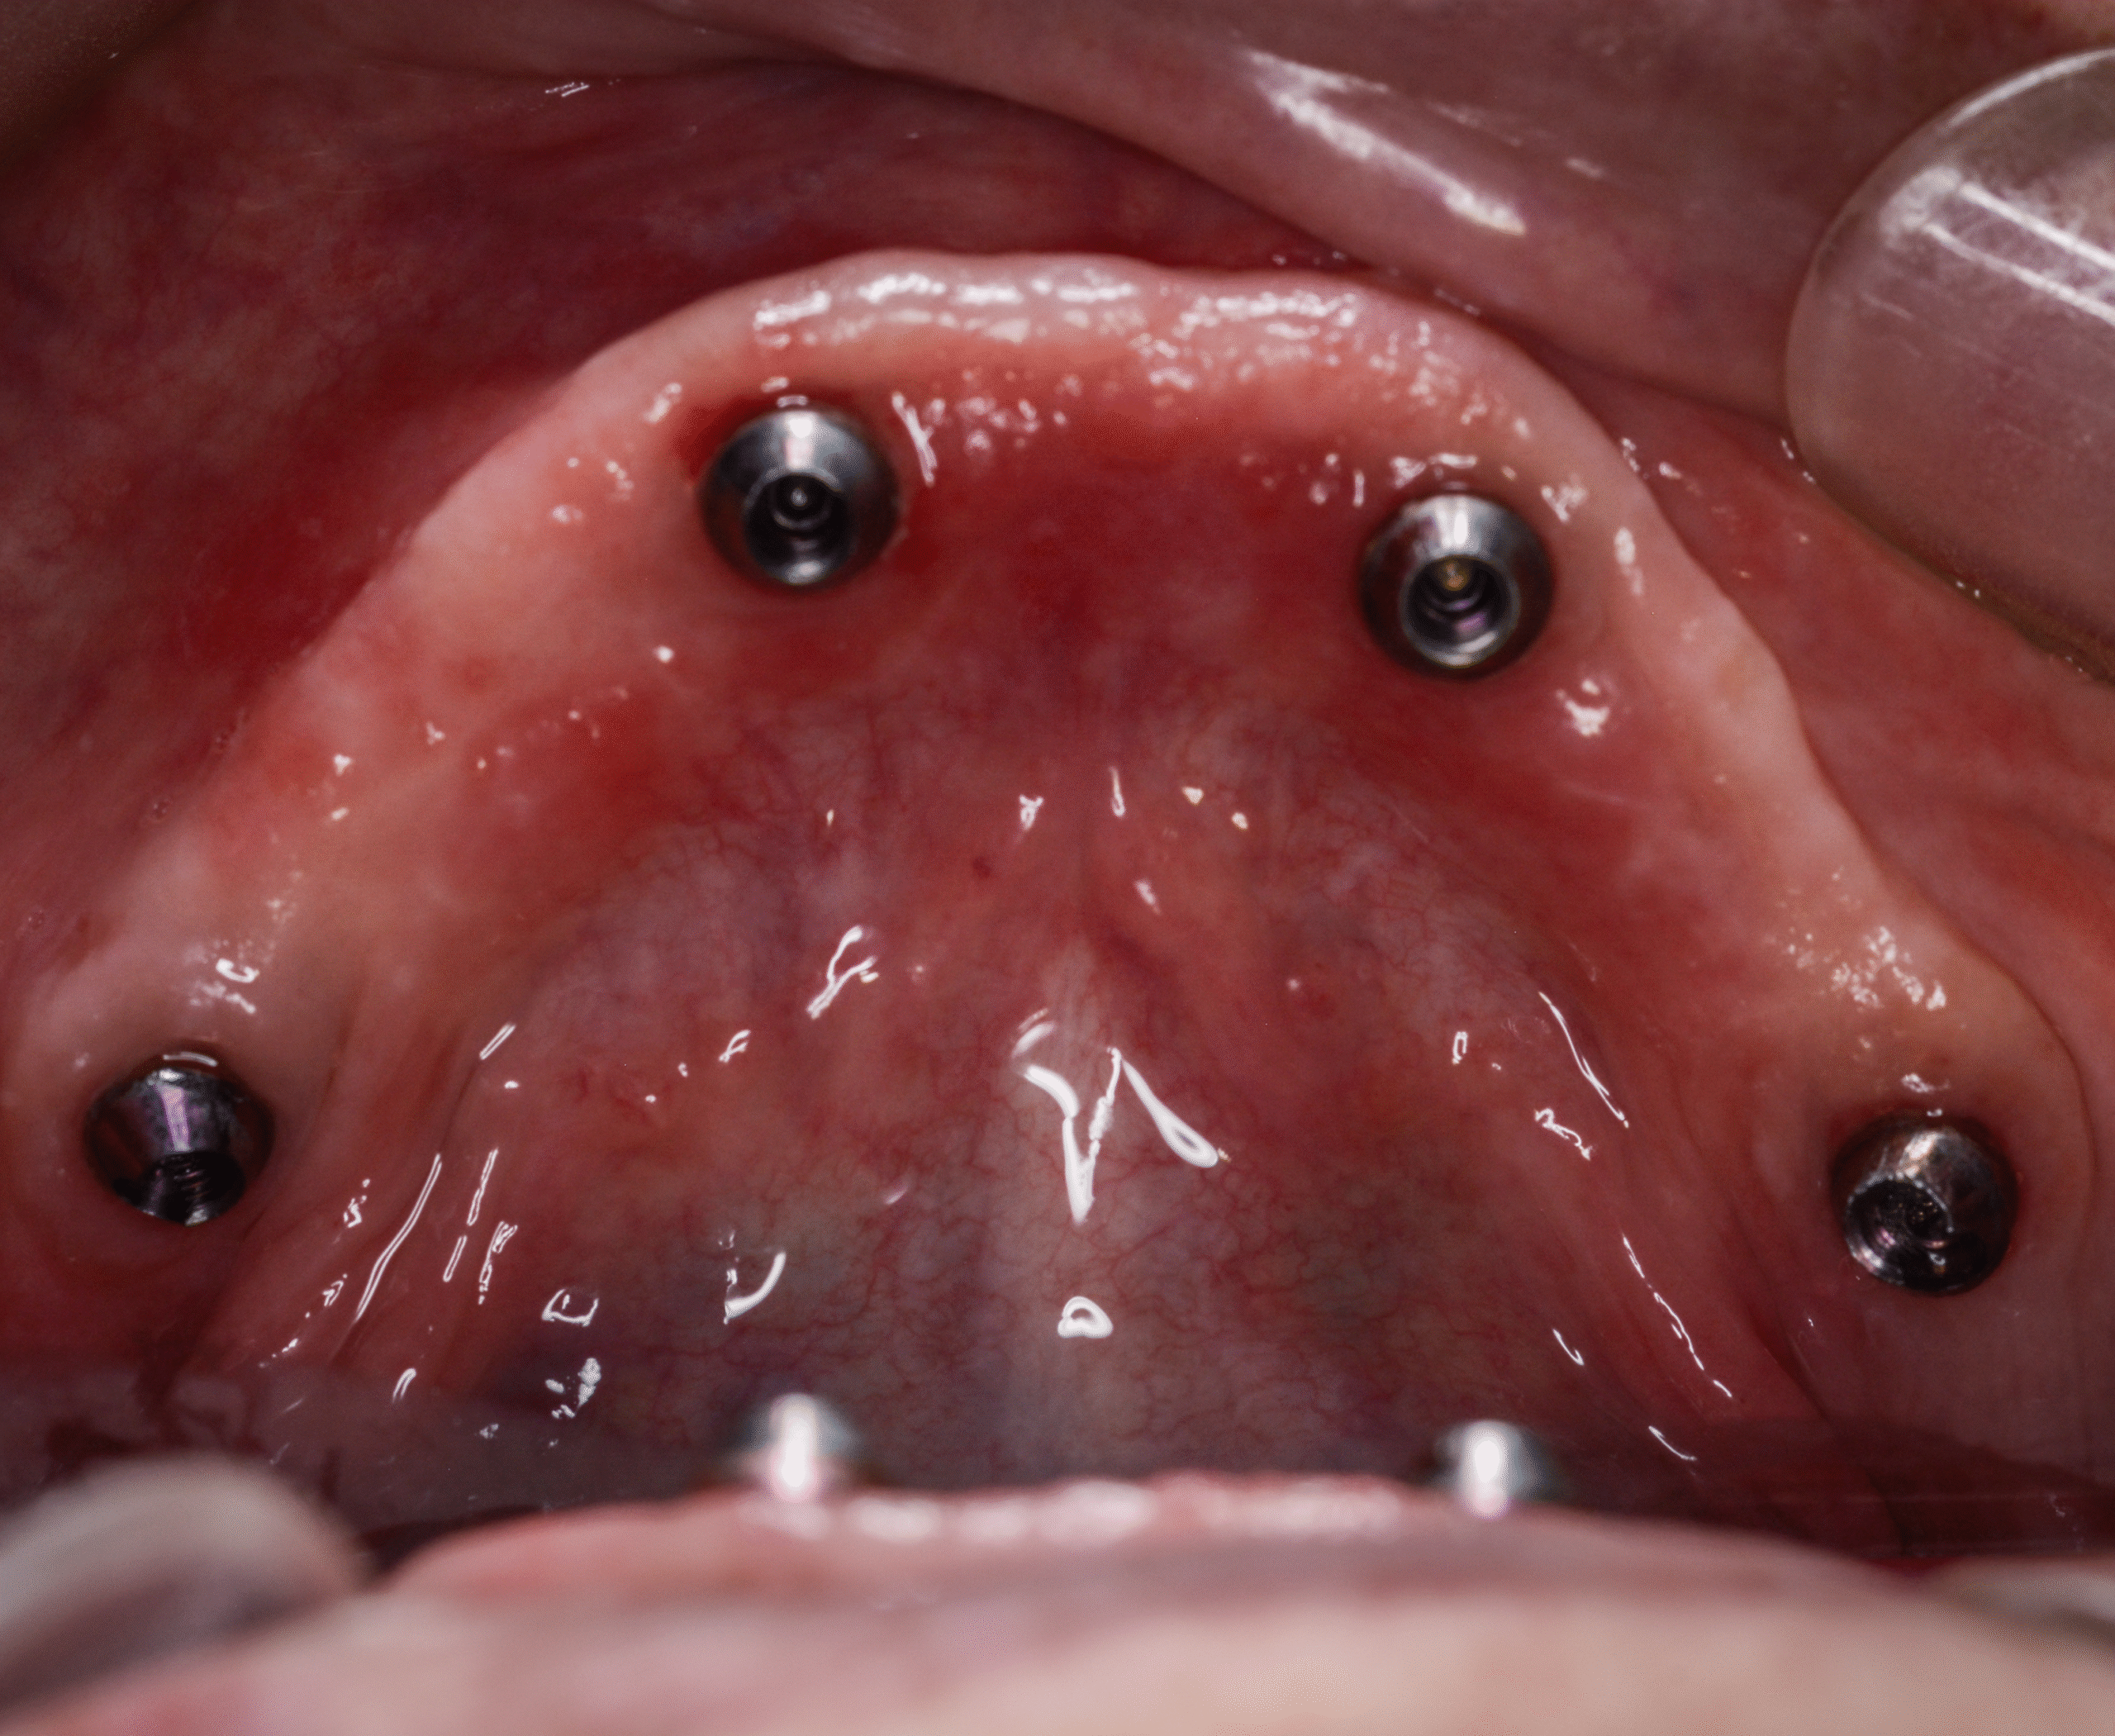

- Placement of four strategically positioned implants

- Achieved strong primary stability, suitable for immediate loading